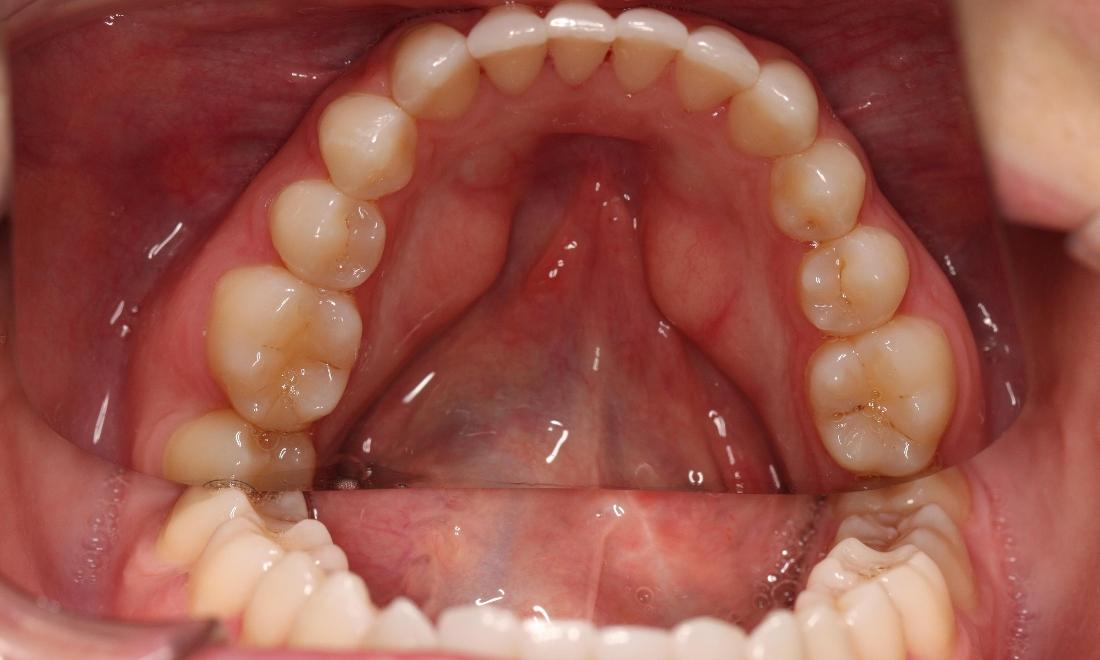

This young woman was self conscious about the crowding in her upper and lower teeth. After months of invisalign treatment, she is very satisfied with the result.